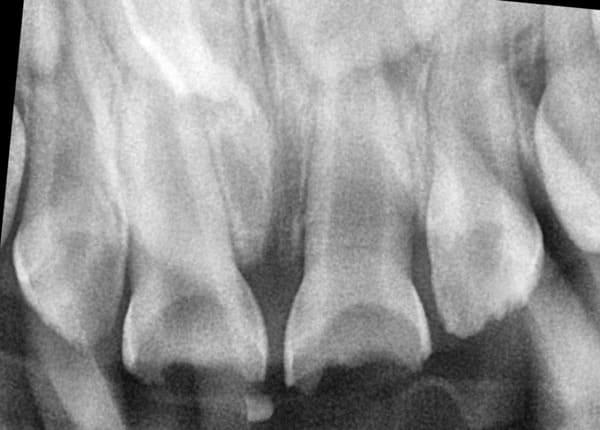

Система кореневих каналів молочних зубів часто складніша, ніж у постійних. Тому ми використовуємо ізоляцію робочого поля за допомогою кофердаму та спеціальне обладнання, щоб гарантувати високу якість лікування.